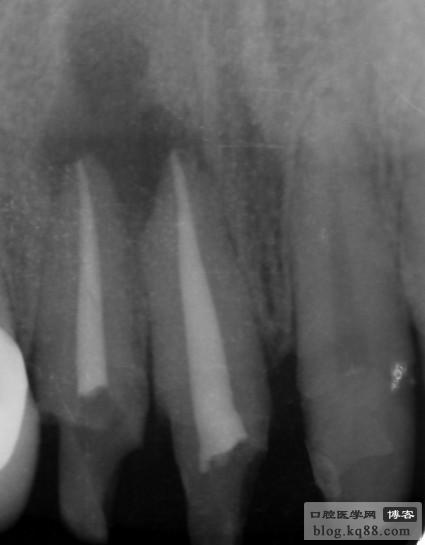

上頜中切牙及側(cè)切牙

左上中切牙